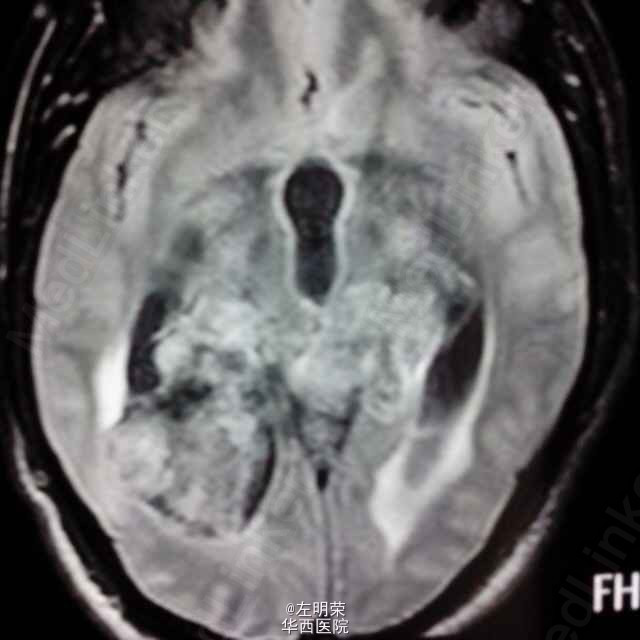

中年男性患者,“反复头痛一年”入院。查体未见明显异常;头部MRI示:松果体区占位,梗阻性脑积水。术中见病变位于右侧脑室三角区,病变范围广泛,侵及丘脑,脑干背侧,松果体区,呈白色珍珠状,质脆,切除过程中出血少,有白色坚韧包膜,予以全切,患者术后恢复良好;病理结果:松果体区表皮样囊肿。